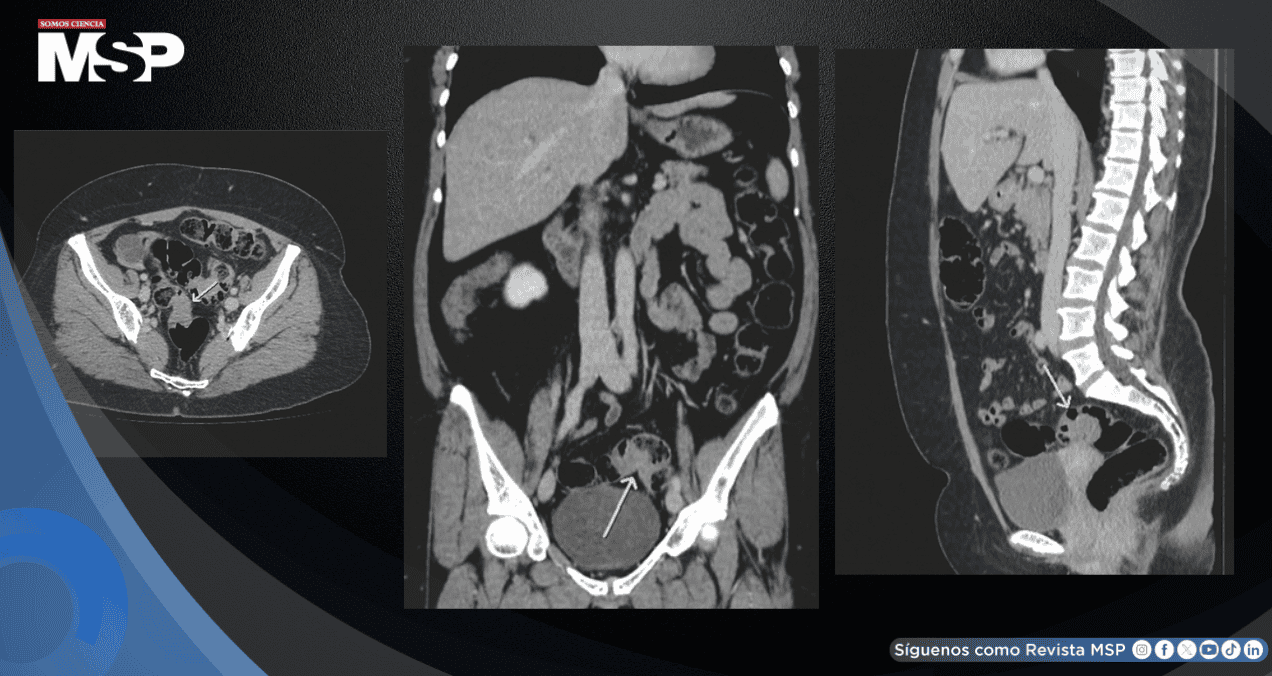

Las investigaciones se iniciaron con pruebas de laboratorio que incluyeron hemograma completo, función renal, electrolitos y pruebas de función hepática, todas las cuales resultaron normales. Posteriormente, se realizó una tomografía computarizada de abdomen que reveló dos áreas de engrosamiento parietal irregular.

La primera se localizaba en el recto superior, con una extensión aproximada de 3 centímetros, mientras que la segunda se encontraba en el segmento medio del colon sigmoide, midiendo alrededor de 2.5 centímetros de longitud.

Ambas lesiones presentaban impregnación con contraste y mostraban características estenosantes, aunque no determinaban una obstrucción intestinal significativa aguas arriba.

Entre las posibilidades diagnósticas consideradas inicialmente, destacaba la sospecha de una neoplasia colorrectal sincrónica, es decir, dos tumores primarios simultáneos.

En este caso concreto, se encontraron dos áreas de engrosamiento parietal irregular, una en el recto superior y otra en el colon sigmoide, que inicialmente se interpretaron como sospechosas de neoplasia sincrónica pero que, tras los hallazgos histológicos, resultaron compatibles con endometriosis infiltrativa profunda.